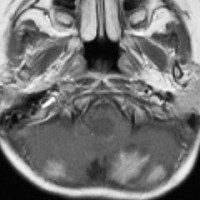

この例は,小脳半球にできたものです。のう胞(水たまり)を形成しています。髄芽腫の大きな特徴は,造影剤を入れないCT(左側)で腫瘍が少し白く見えることです(灰白質より高密度といいます)。細胞密度が高いので高密度になります。この例はclassic medulloblastomaですが,MIB-1は45%に達するもので,急激な腫瘍発育を示します。